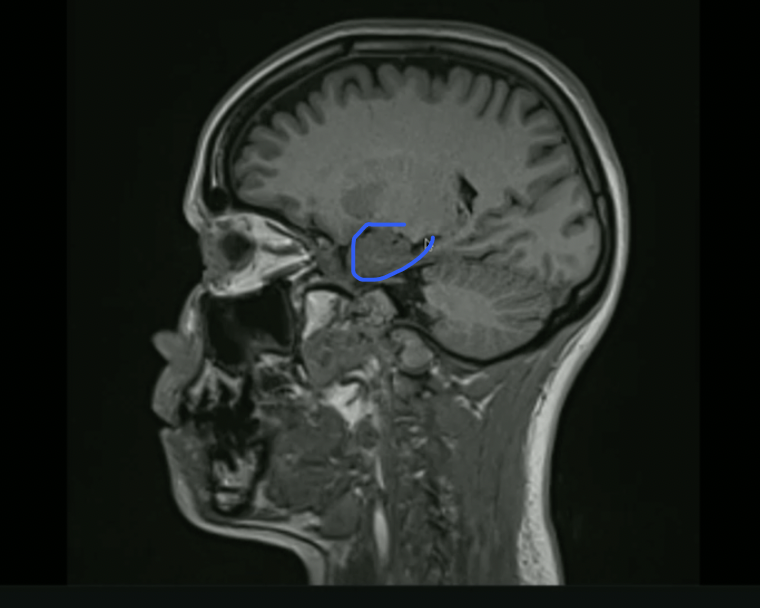

<p>What is this? + Pathway to it</p>

What is this? + Pathway to it

• Hippocampus

• Mammilary Body → Fornix → Hippocampus